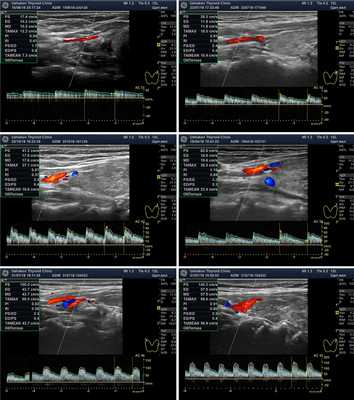

Рисунок 5. Варианты Пиковой Систолической Скорости Кровотока (ПССК). Спектральная допплеровская диагностика кровотока щитовидной железы. Представлены основные случаи ПССК: Ослабленная, Нормальная, Малого усиления, Умеренного усиления, Значительного и Очень значительного усиления.